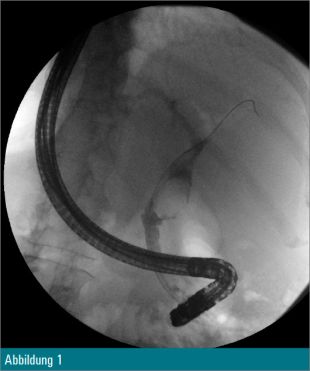

Eine 55-jährige Patientin wurde wegen eines Tonnenkonkrements im Ductus choledochus zur ERCP vorstellig (Abbildung 1). Nach Papillotomie erfolgte zusätzlich eine Ballondilatation der Papille auf 12 mm. Anschließend wurde mit dem Cholangioskop in den Ductus choledochus eingegangen (Abbildung 2) und eine elektrohydraulische Zertrümmerung des Konkrements unternommen (Abbildung 3).

Trotz Fragmentierung des Konkrements (Abbildung 4) waren mehrfache mechanische Lithotripsien mit dem Dormiakörbchen in derselben Sitzung notwendig. Schlussendlich konnten alle Fragmente erfolgreich mit dem Ballon geborgen werden (Abbildung 5).